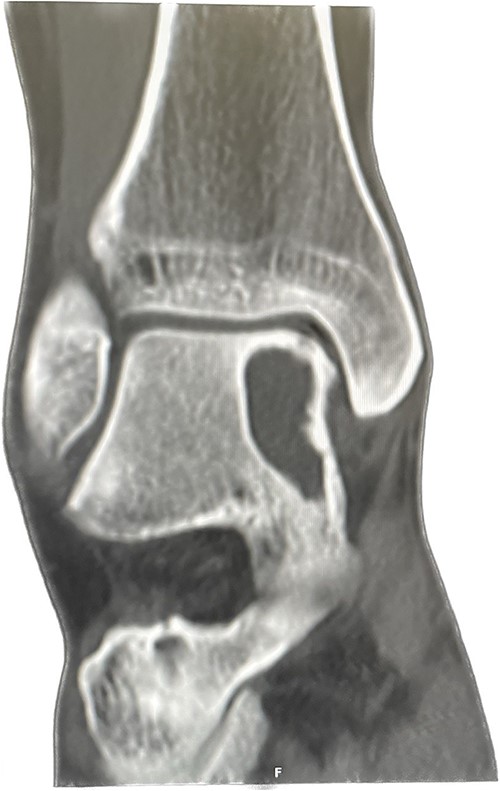

An X-ray of the ankle showed a radiolucency at the anteromedial aspect of the talus, suggesting a subchondral cyst. This lesion measured 18 × 18 × 11 mm on the CT scan in the medial patellar dome with a focal vacuum at the medial talocrural joint. The overlying cortex was thinned out with medial focal cortical defect. There was no collapse of the articular surface (Fig. 1).